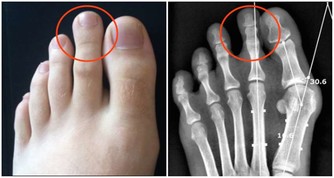

大量的生長激素會刺激骨關節異常增生,侵犯膝、踝、腕等大關節,出現腫脹、疼痛等症狀。

據報導,老年人肺癌合併關節痛的發生率約佔10%至20%。

因此,對中、老年人突然逐漸加重的肩臂痛,無論是否伴有呼吸道症狀,

且肩臂痛經牽引或止痛藥治療,只能暫時緩解症狀而不能阻止疼痛進行性加重時,就需高度警惕。